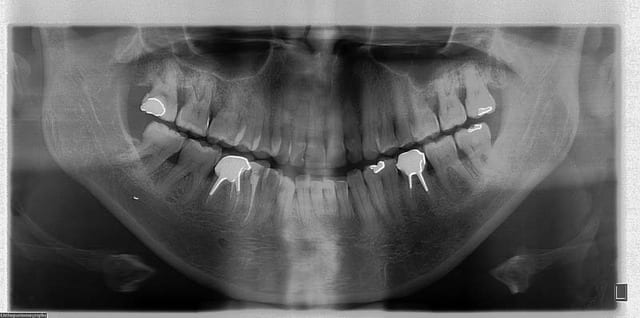

pas de Pbs. psy, voici les Rx.

douleurs coté G.

@+ Bjc.

les radio ds les troubles de ce genre ne st pas vraiment concluantes mais on vois une pte irrégularité condylienne qui me fait penser à l'arthrose

"""la 36 est elle en sur guidage dans les fonctions de latéralité gauche,"""

a l’examen clinique, il ne semble pas, il faudra un montage sur articulateur pour confirmer

regarde aussi les 16/26